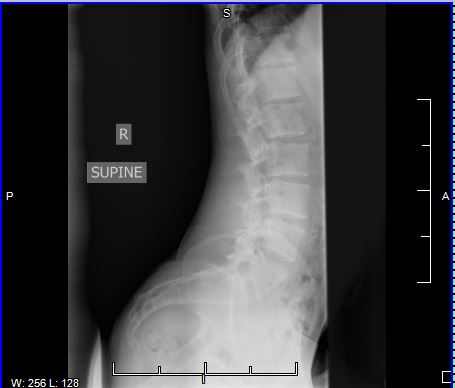

So this is my spine when I'm bent over

Are my low back muscles probably too tight/compressed or could it be something else? This is me lying down on my side and the curve is still there so what do I do?